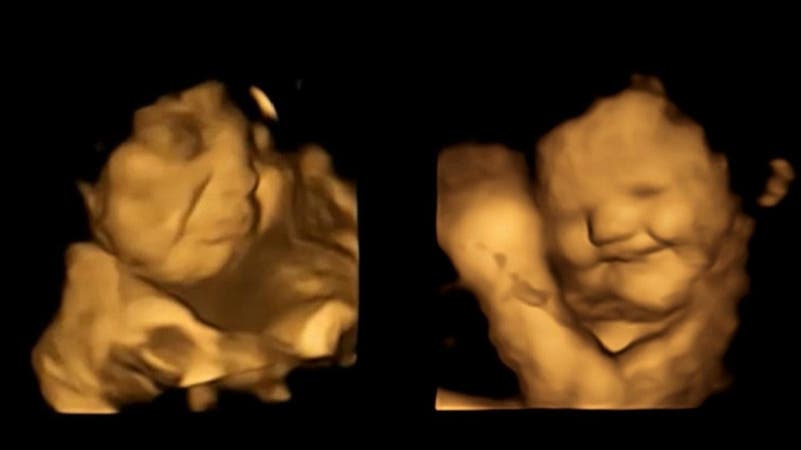

في دراسة مذهلة تمكن علماء من رصد وجوه الأجنة وهم يتناولون الطعام في بطون أمهاتهم بسبب نوعية الطعام ،فقد لاحظوا أن الجنين يبتسم حين يتذوق الجزر ويعبس عندما يكون اللفت والكرنب أو هو الطعام،

وكشفت الدراسة أن الأجنة في الرحم يتفاعلون بشكل إيجابي مع أمهاتهم اللواتي يأكلن الجزر، ولكنهم يبكون بعد تناول الأمهات للخضروات الخضراء.

وبحسب شبكة "سكاي نيوز" البريطانية، قام الباحثون في جامعة "دورهام" بأخذ موجات فوق صوتية رباعية الأبعاد لـ100 امرأة حامل، بعد 20 دقيقة من تناول أقراص مليئة إما بمسحوق الجزر وإما بالكرنب.

ووجدوا أن الأجنة التي تناولت أمهاتها أقراص الجزر تبتسم بعد ذلك بوقت قصير، لكن مسح النساء اللواتي تناولن أقراص الكرنب أظهر أن أطفالهن يبكون.

الدراسة التي نُشرت في مجلة "فيزيولوجيكال ساينس"، هي الأولى في العالم التي تبحث في كيفية تفاعل الأجنة مع التذوق والشم قبل ولادتها.

ويُعتقد أن الأجنة تتذوق نكهة طعام أمهاتهم عن طريق استنشاق أو ابتلاع السائل الأمنيوسي في الرحم.

وقالت بيزا أوستون، التي قادت البحث: "دراستنا هي الأولى التي شاهدت ردود الفعل هذه قبل الولادة، كان من المدهش حقا رؤية تفاعل الأطفال الذين لم يولدوا بعد مع نكهات الكرنب أو الجزر أثناء الفحص ومشاركة تلك اللحظات مع الوالدين".